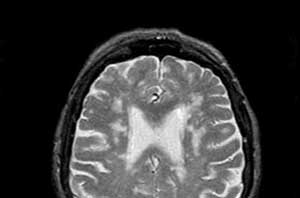

Диагностика

Для установления диагноза «лейкоэнцефалопатия» специалист проведет всестороннее обследование. В этом процессе потребуются:

- магнитно-резонансная и компьютерная томография, которые помогут выявить патологические изменения в головном мозге;